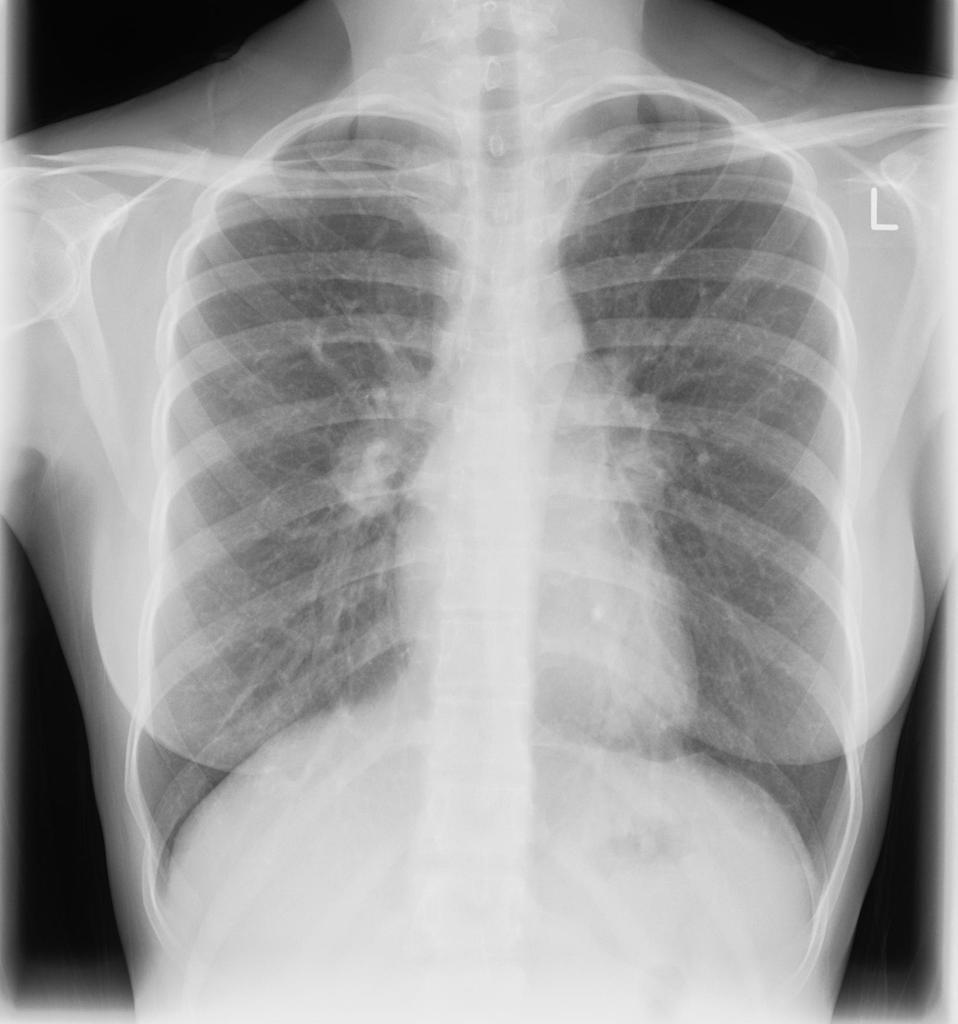

Describe the abnormality/ies

Cardiomegaly